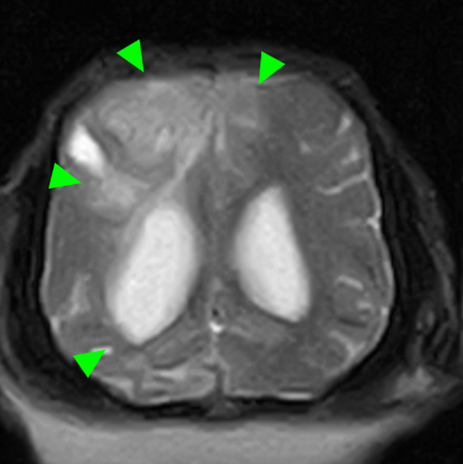

神経内科

神経外科

MRI